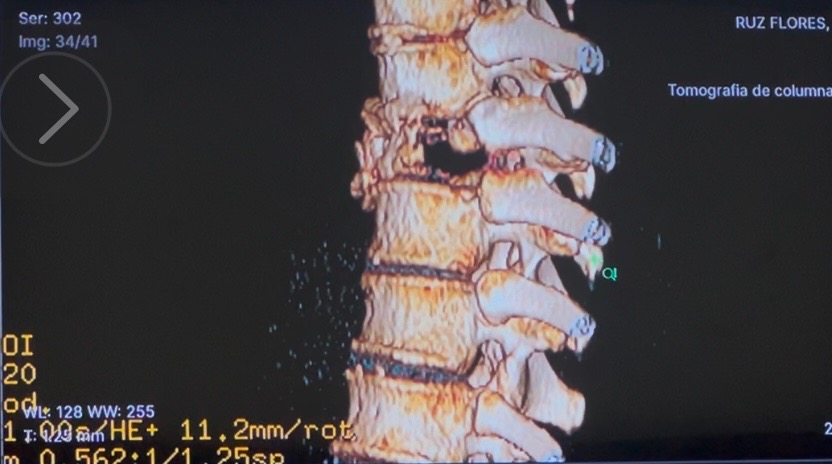

El pasado 31 de mayo de 2025, mientras viajaba en moto con mi padre, fuimos brutalmente atropellados. Yo llevaba casco, iba con precaución… pero la violencia del impacto me cambió la vida en segundos. Desde entonces, vivo con fracturas en mis costillas, una lesión lumbar y una fractura severa en la vértebra T8, que amenaza con dejarme sin movilidad si no recibo atención médica especializada de inmediato.

Diagnóstico actual: Fractura vertebral T8 postraumática con compromiso estructural grave + fracturas costales + protrusión discal lumbar